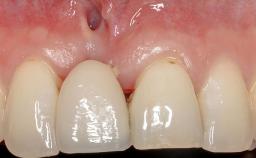

Soft-Tissue Volume Augmentation Using a Connective-Tissue Graft Harvested from the Maxillary Tuberosity

In 1983, a 51-year-old non-smoking patient was referred for the treatment of moderate chronic periodontitis. At the initial examination, 47% of sites exhibited probing depths of 4 to 6 mm. Periodontal therapy consisted of initial periodontal treatment including oral-hygiene instructions and supra- and subgingival debridement, followed by periodontal surgery to eliminate residual pockets.

| Soft Tissue Grafting | Simultaneous |